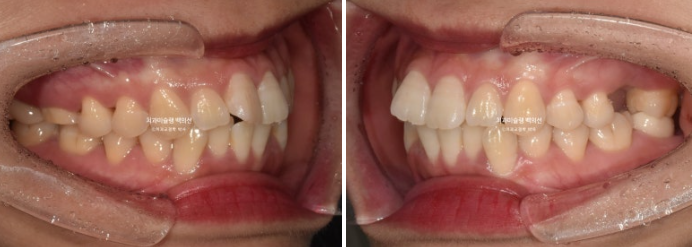

23년 10월 교정을 위해 온 30대 환자분입니다.

앞니는 뻗쳐있고 좌측 큰어금니 자리가 비어있습니다.

아래 앞니는 삐뚤하여 배열할 공간이 필요하고

위 첫번째 큰어금니 (제1대추치)가 한쪽은 발치되어있고 한쪽은 아직 발치는 안 했지만 발치진단이 나온 상황입니다.

환자분의 돌출감을 고려했을 때 작은어금니 발치교정이 맞지만 환자분은 작은어금니 발치까지는 원하지 않으셨습니다.

작은어금니 발치 없이 사랑니 공간만을 이용하는 비발치 돌출입 교정은 그 효과가 드라마틱하진 않겠지만, 이미 충치로 큰어금니 2개를 잃은 상황에서는 작은어금니 발치가 부담이 될 수 있습니다.